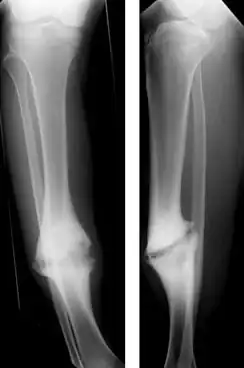

| Hypertrophic nonunion of the tibia | |

Hypertrophic nonunion

In a hypertrophic nonunion, the fracture site contains adequate blood supply but the fracture ends fail to heal together.[6] X-rays show abundant callus formation. This type of nonunion is thought to occur when the body has adequate biology, such as stem cells and blood supply, but inadequate stability, meaning the bone ends are moving too much. Typically, the treatment consists of increasing stability of the fracture site with surgical implants.[7]